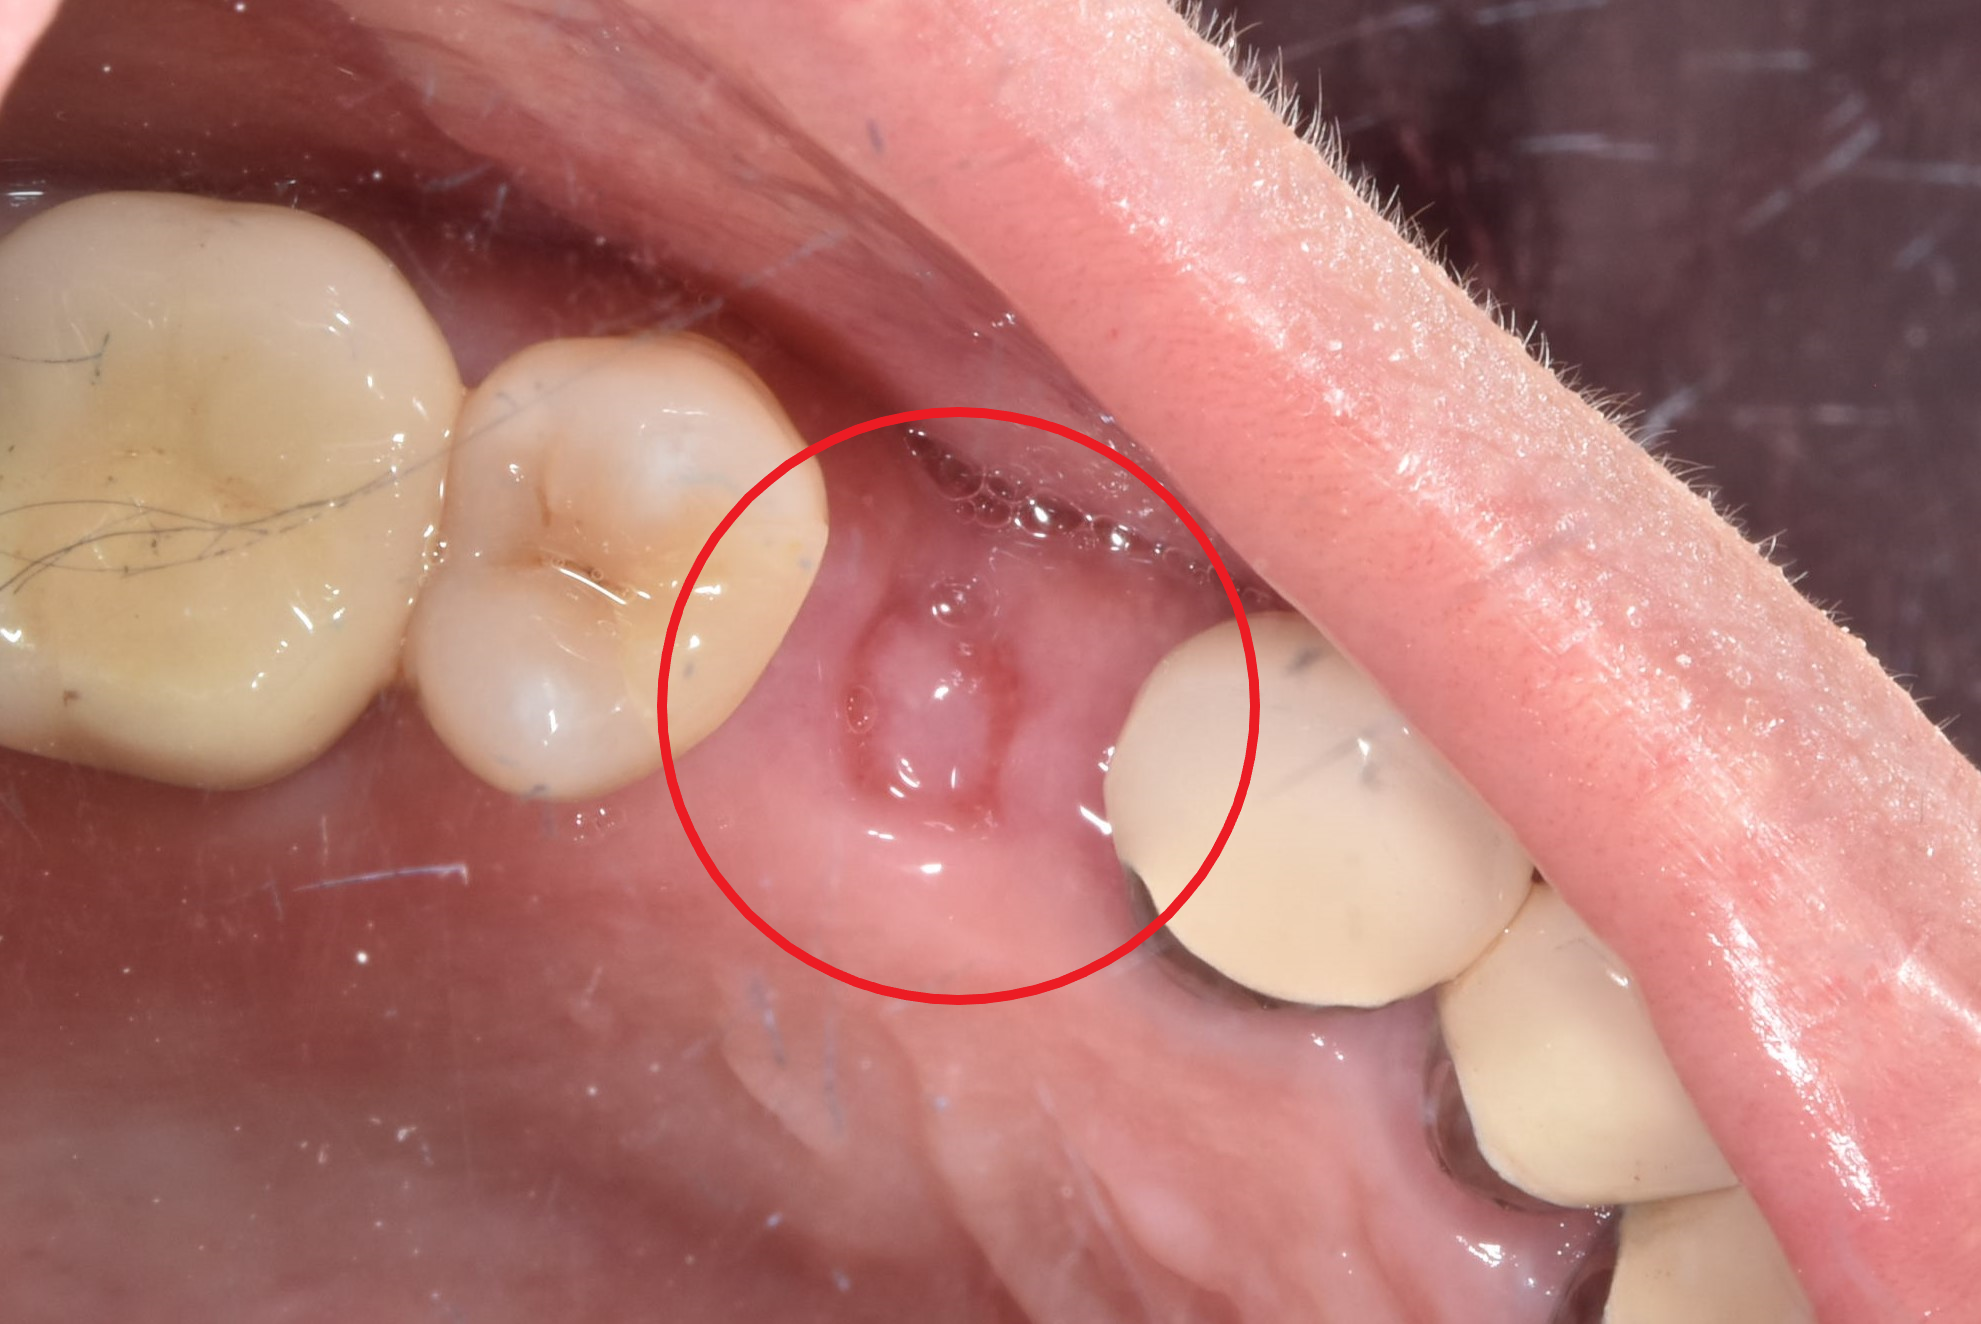

骨頭明顯凹陷